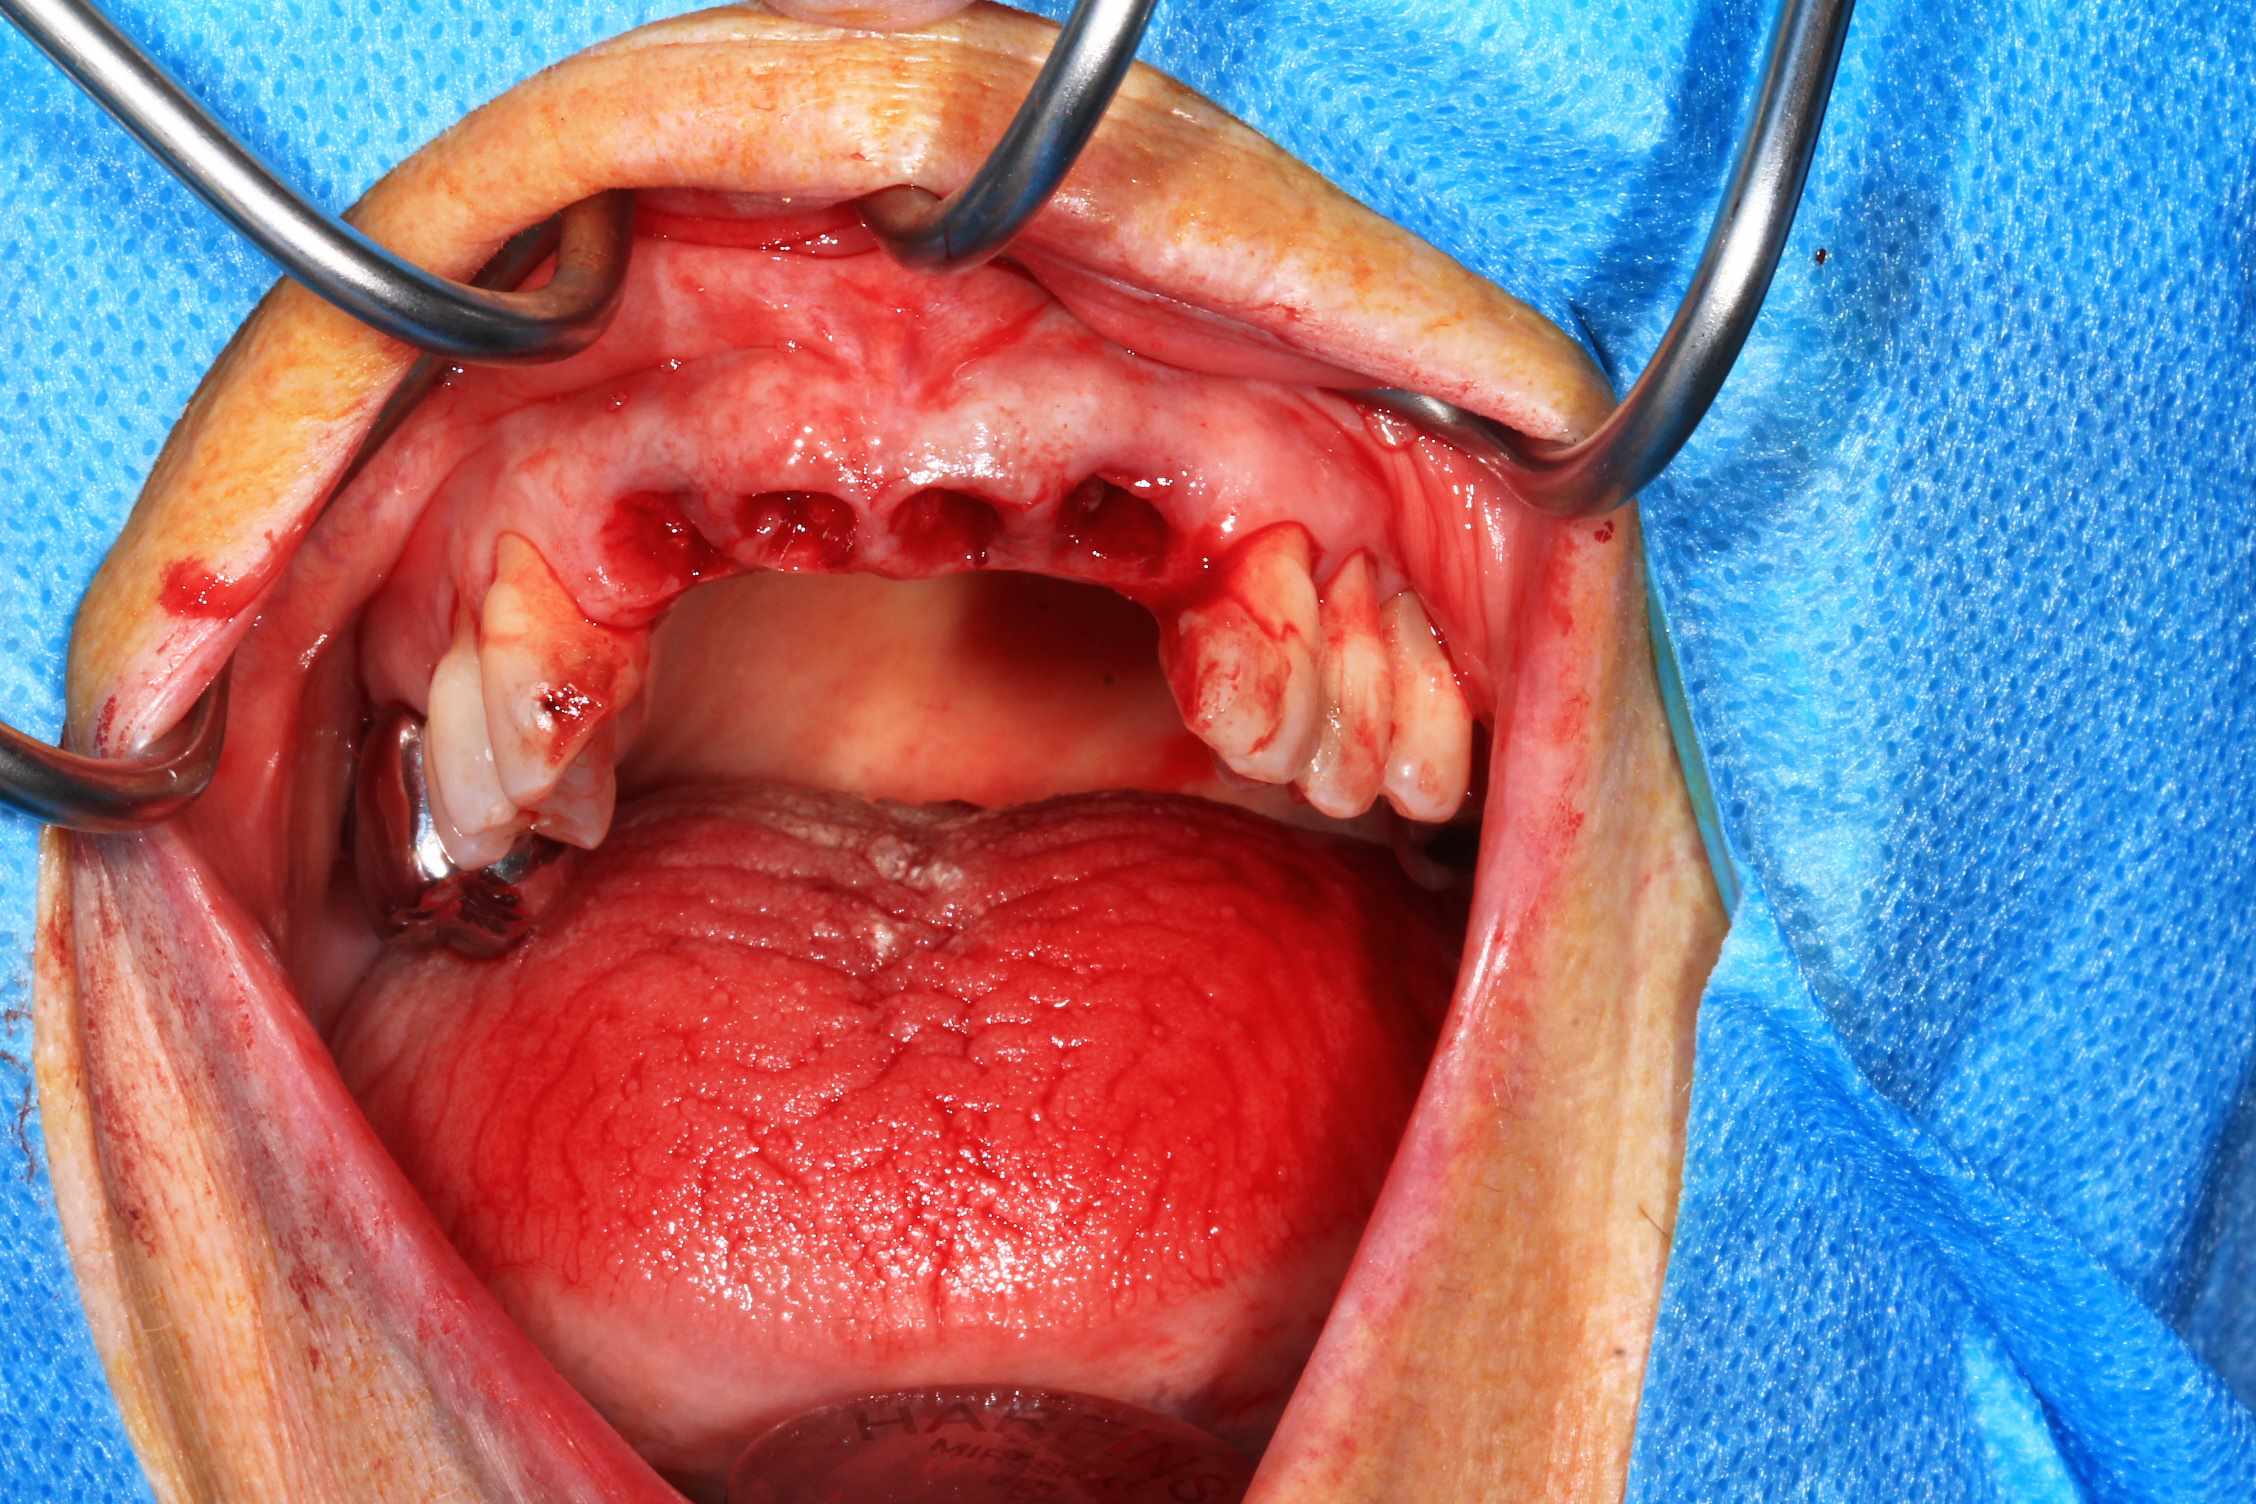

les 4 incisives sup sont à bout de souffle . Planification et export du guide résine avec blueskyplan. Export du modèle osseux et simulation de la chirurgie, comme d'hab selon mon protocole.

Quand les implants sont peu nombreux et proches, un guide résine est suffisant. C'est alors beaucoup plus rapide.

Pré-op :

Chir : extraction, implant flapless et pose du bridge imprimé Flexera rosenscrew.